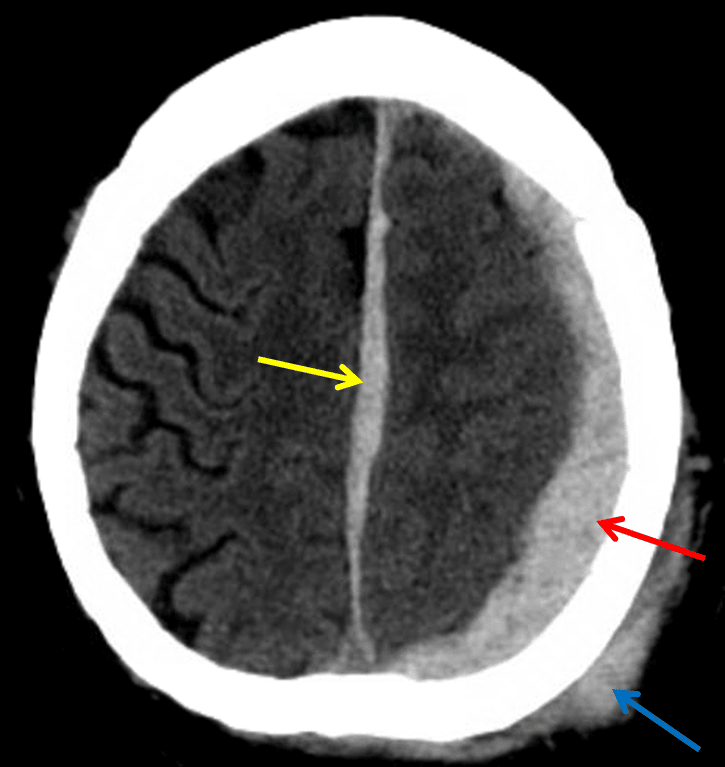

• Acute subdural hematoma measuring up to 11 mm in thickness layering over the left cerebral convexity with a smaller portion extending over the left tentorium and interhemispheric falx

• Diffuse left cerebral hemispheric sulcal effacement with 6 mm left to right midline shift

• Left posterior scalp hematoma

Red arrow: acute subdural hematoma layering along the left cerebral convexity. Yellow arrow: subdural hematoma layering along the interhemispheric falx. Blue arrow: scalp hematoma.